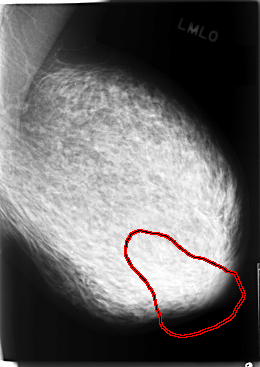

C_0078_1.LEFT_MLO

LEFT_MLO LINES 5864 PIXELS_PER_LINE 4152 BITS_PER_PIXEL 12 RESOLUTION 50 OVERLAY

FILE: C_0078_1.LEFT_MLO.OVERLAY

TOTAL_ABNORMALITIES 1

ABNORMALITY 1

LESION_TYPE CALCIFICATION TYPE PLEOMORPHIC DISTRIBUTION CLUSTERED

ASSESSMENT 5

SUBTLETY 5

PATHOLOGY MALIGNANT

TOTAL_OUTLINES 1

BOUNDARY